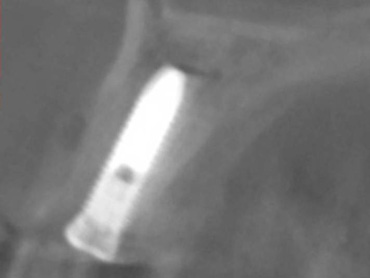

| ガイドを使用した実際のインプラント埋入手術 | 術前の3Dシミュレーション画像 |

ノーベルガイドを使用した実際のインプラント埋入症例。手術中の様子、術前の3Dシミュレーション画像、インプラント埋入手術後のCT画像です。 手術前後の2つの画像を合わせてみるとほぼ完全に一致します。これがノーベルガイドが現在最も安全で正確なインプラントシステムであると言われる理由です。 |

インプラント埋入位置や

上部構造の形態などの治療計画を3Dで作成します。 |

上顎の歯を全て失ってしまいインプラントをご希望にて上顎に6本のインプラントを埋入し(ボーンアンカードブリッジ)治療を行いました。コンピューターガイドシステムを用いることで、補綴的にも外科的にも最善な位置にインプラントのポジショニングを行うことができます。 また外科的な侵襲を最小限に抑えることができるだけでなく、手術をきわめて短時間で終わらせることができ、患者さんの肉体的負担を軽減することが可能です。さらに埋入手術を行ったその日に固定式の仮歯を装着することができます。 |